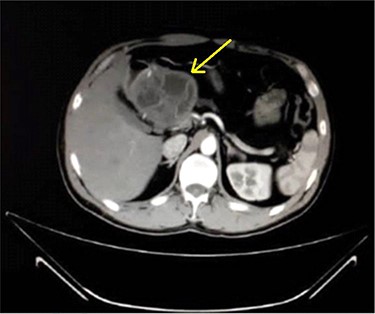

A 33-year-old male was referred to our Department of General Surgery, with a 3-month severe epigastric pain radiating to the back, associated with several episodes of green vomiting. Pain is episodic, relieved by painkillers, has no relation to food or movement. No history of changes in bowel habits or urine color. The patient reported a history of early satiety and an observed unmeasured weight loss. The past medical and surgical histories were irrelevant. Abdominal examination showed tenderness in the epigastric region, with no other signs. Laboratory tests including complete blood cell count, renal and liver function tests were within normal levels. Immunologic methods (ELISA) and indirect hemagglutination (IHA) assays were negative. Serum Amylase and CA 19-9 were within normal levels. Computed tomography (CT) scan revealed a multilocular cystic lesion in the head of the pancreas measuring 9.5 × 8.2 × 11 cm, causing external compression on the distal part of the CBD. The main pancreatic duct near the cystic mass is dilated measuring 0.5 cm. The gallbladder is distended (Figs 1 and 2).

Axial contrast-enhanced CT scan of the abdomen demonstrating a well-defined solitary cystic lesion in the head of the pancreas with a diameter of (9 cm).